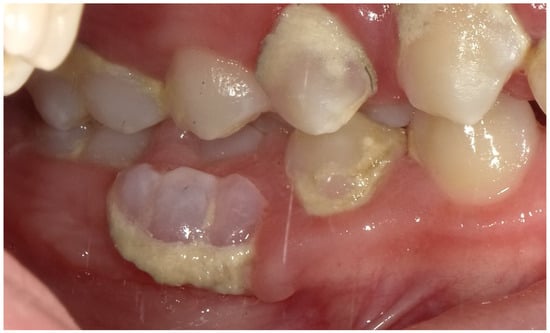

2.2. Clinical Findings

2.3. Diagnostic Assessment

2.4. Therapeutic Intervention